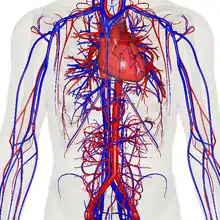

- There’s no evidence yet to suggest any ethnic group is at greater risk of complications from the coronavirus because of a lack of immunity since the virus is new to all humans, said Dr. Jehan El-Bayoumi, founding director of the Rodham Institute at the George Washington University.

But other social and economic factors — such as nutrition, access to health care and poverty — do increase the risk of complications in indigenous and minority communities, El-Bayoumi said.

Of note, the seroprevalence in the routine care group (as well as the urgent care group at the end of May, after the peak) falls significantly below the threshold for potential community immunity, which has been estimated by one study to require at least a seropositivity rate of 67% for SARS-CoV-24. On the basis of the population of NYC (8.4 million), we estimate that by the week ending 24 May, approximately 1.7 million individuals had been infected with SARS-CoV-2. Taking into account the cumulative number of deaths in the city by 19 May (16,674—this number includes only officially confirmed, not suspected, COVID-19-related deaths), this suggests a preliminary infection fatality rate of 0.97% (with the assumption that both seroconversion and death occur with similar delays). This is in stark contrast to the infection fatality rate of the 2009 H1N1 pandemic, which was estimated to be 0.01–0.001%.- Daniel Stadlbauer, Jessica Tan, Kaijun Jiang, Matthew M. Hernandez, Shelcie Fabre, Fatima Amanat, Catherine Teo, Guha Asthagiri Arunkumar, Meagan McMahon, Christina Capuano, Kathryn Twyman, Jeffrey Jhang, Michael D. Nowak, Viviana Simon, Emilia Mia Sordillo, Harm van Bakel & Florian Krammer; “Repeated cross-sectional sero-monitoring of SARS-CoV-2 in New York City”, Nature, (03 November 2020)

And as with SARS-CoV, MERS-CoV and animal coronaviruses, the damage doesn’t stop with the lungs. A SARS-CoV-2 infection can trigger an excessive immune response known as a cytokine storm, which can lead to multiple organ failure and death. The virus can also infect the intestines, the heart, the blood, sperm (as can MERS-CoV), the eye and possibly the brain. Damage to the kidney, liver and spleen observed in people with COVID-19 suggests that the virus can be carried in the blood and infect various organs or tissues, says Guan Wei-jie, a pulmonologist at the Guangzhou Institute of Respiratory Health at Guangzhou Medical University, China, an institution lauded for its role in combating SARS and COVID-19. The virus might be able to infect various organs or tissues wherever the blood supply reaches, says Guan.